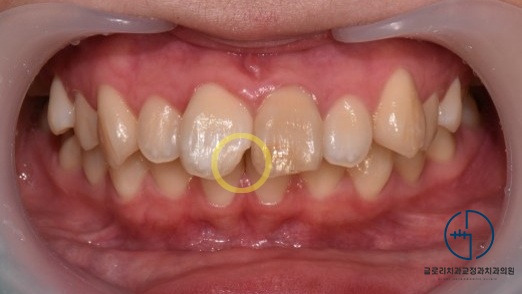

1) 정면

제일 먼저 눈에 띄는 것은 전치부 치아의 파절입니다.

앞니 근심 절단부위가 깨져있었으며,

윗니가 아랫니를 과도하게 덮는 과개교합도 나타나 있었습니다.